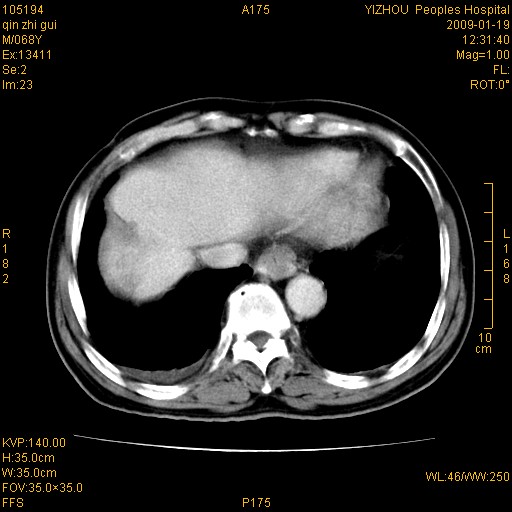

以下是引用随光逐影在2009-1-21 16:11:00的发言:[br]1)考虑肝右叶肝癌并肝静脉及门静脉瘤栓形成。2)肝硬化,少量腹水。3)胆囊炎。4)右侧少量胸腔积液。

病灶外缘凹凸不平,平扫低密度,增强动脉期有强化,门脉早显,静脉期及延期呈延迟强化,结合病史考虑右肝前叶巨块型肝癌可能性大,强化表现不除外胆管细胞癌